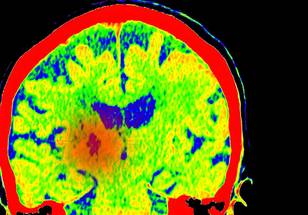

In a major advance for the treatment of the deadly brain cancer glioblastoma, Northwestern Medicine scientists have used ultrasound technology to penetrate the blood-brain barrier and provide a small dose of a chemotherapy and immunotherapy drug cocktail. The study found that this treatment boosted the immune system's recognition of the cancer cells and could lead to a new treatment approach.

Scientists showed for the first time that a skull-implantable ultrasound device can enhance the penetration of the chemotherapy drug doxorubicin and immune checkpoint blockade antibodies—a novel immunotherapy treatment combination—into the human brain. The device produces microbubbles that temporarily open the blood-brain barrier, allowing the immunotherapy to enter the brain.